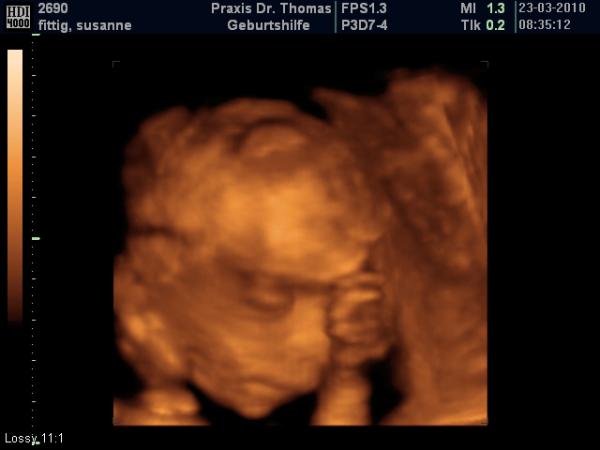

unserem kleinen Mann geht es gut soweit obwohl ich unter vorwehen leide seit dem es wieder stress mit der ex von meinem Mann gab, der Zuckertest war nicht grade angenehm das ganze gepikse dann toko geschrieben und spritze bekommen wegen Rehus negativ und wurde dann doch schließlich mit einem ganz tollen 3 D us belohnt. der Zwerg wiegt jetzt 510 g und ist ca 28 cm groß

könnte ich stunden lang anschauen

ist das nicht ein wunder was man heute so alles von aussen sehen kann? das erleichtert die warterei doch ungemein oder?